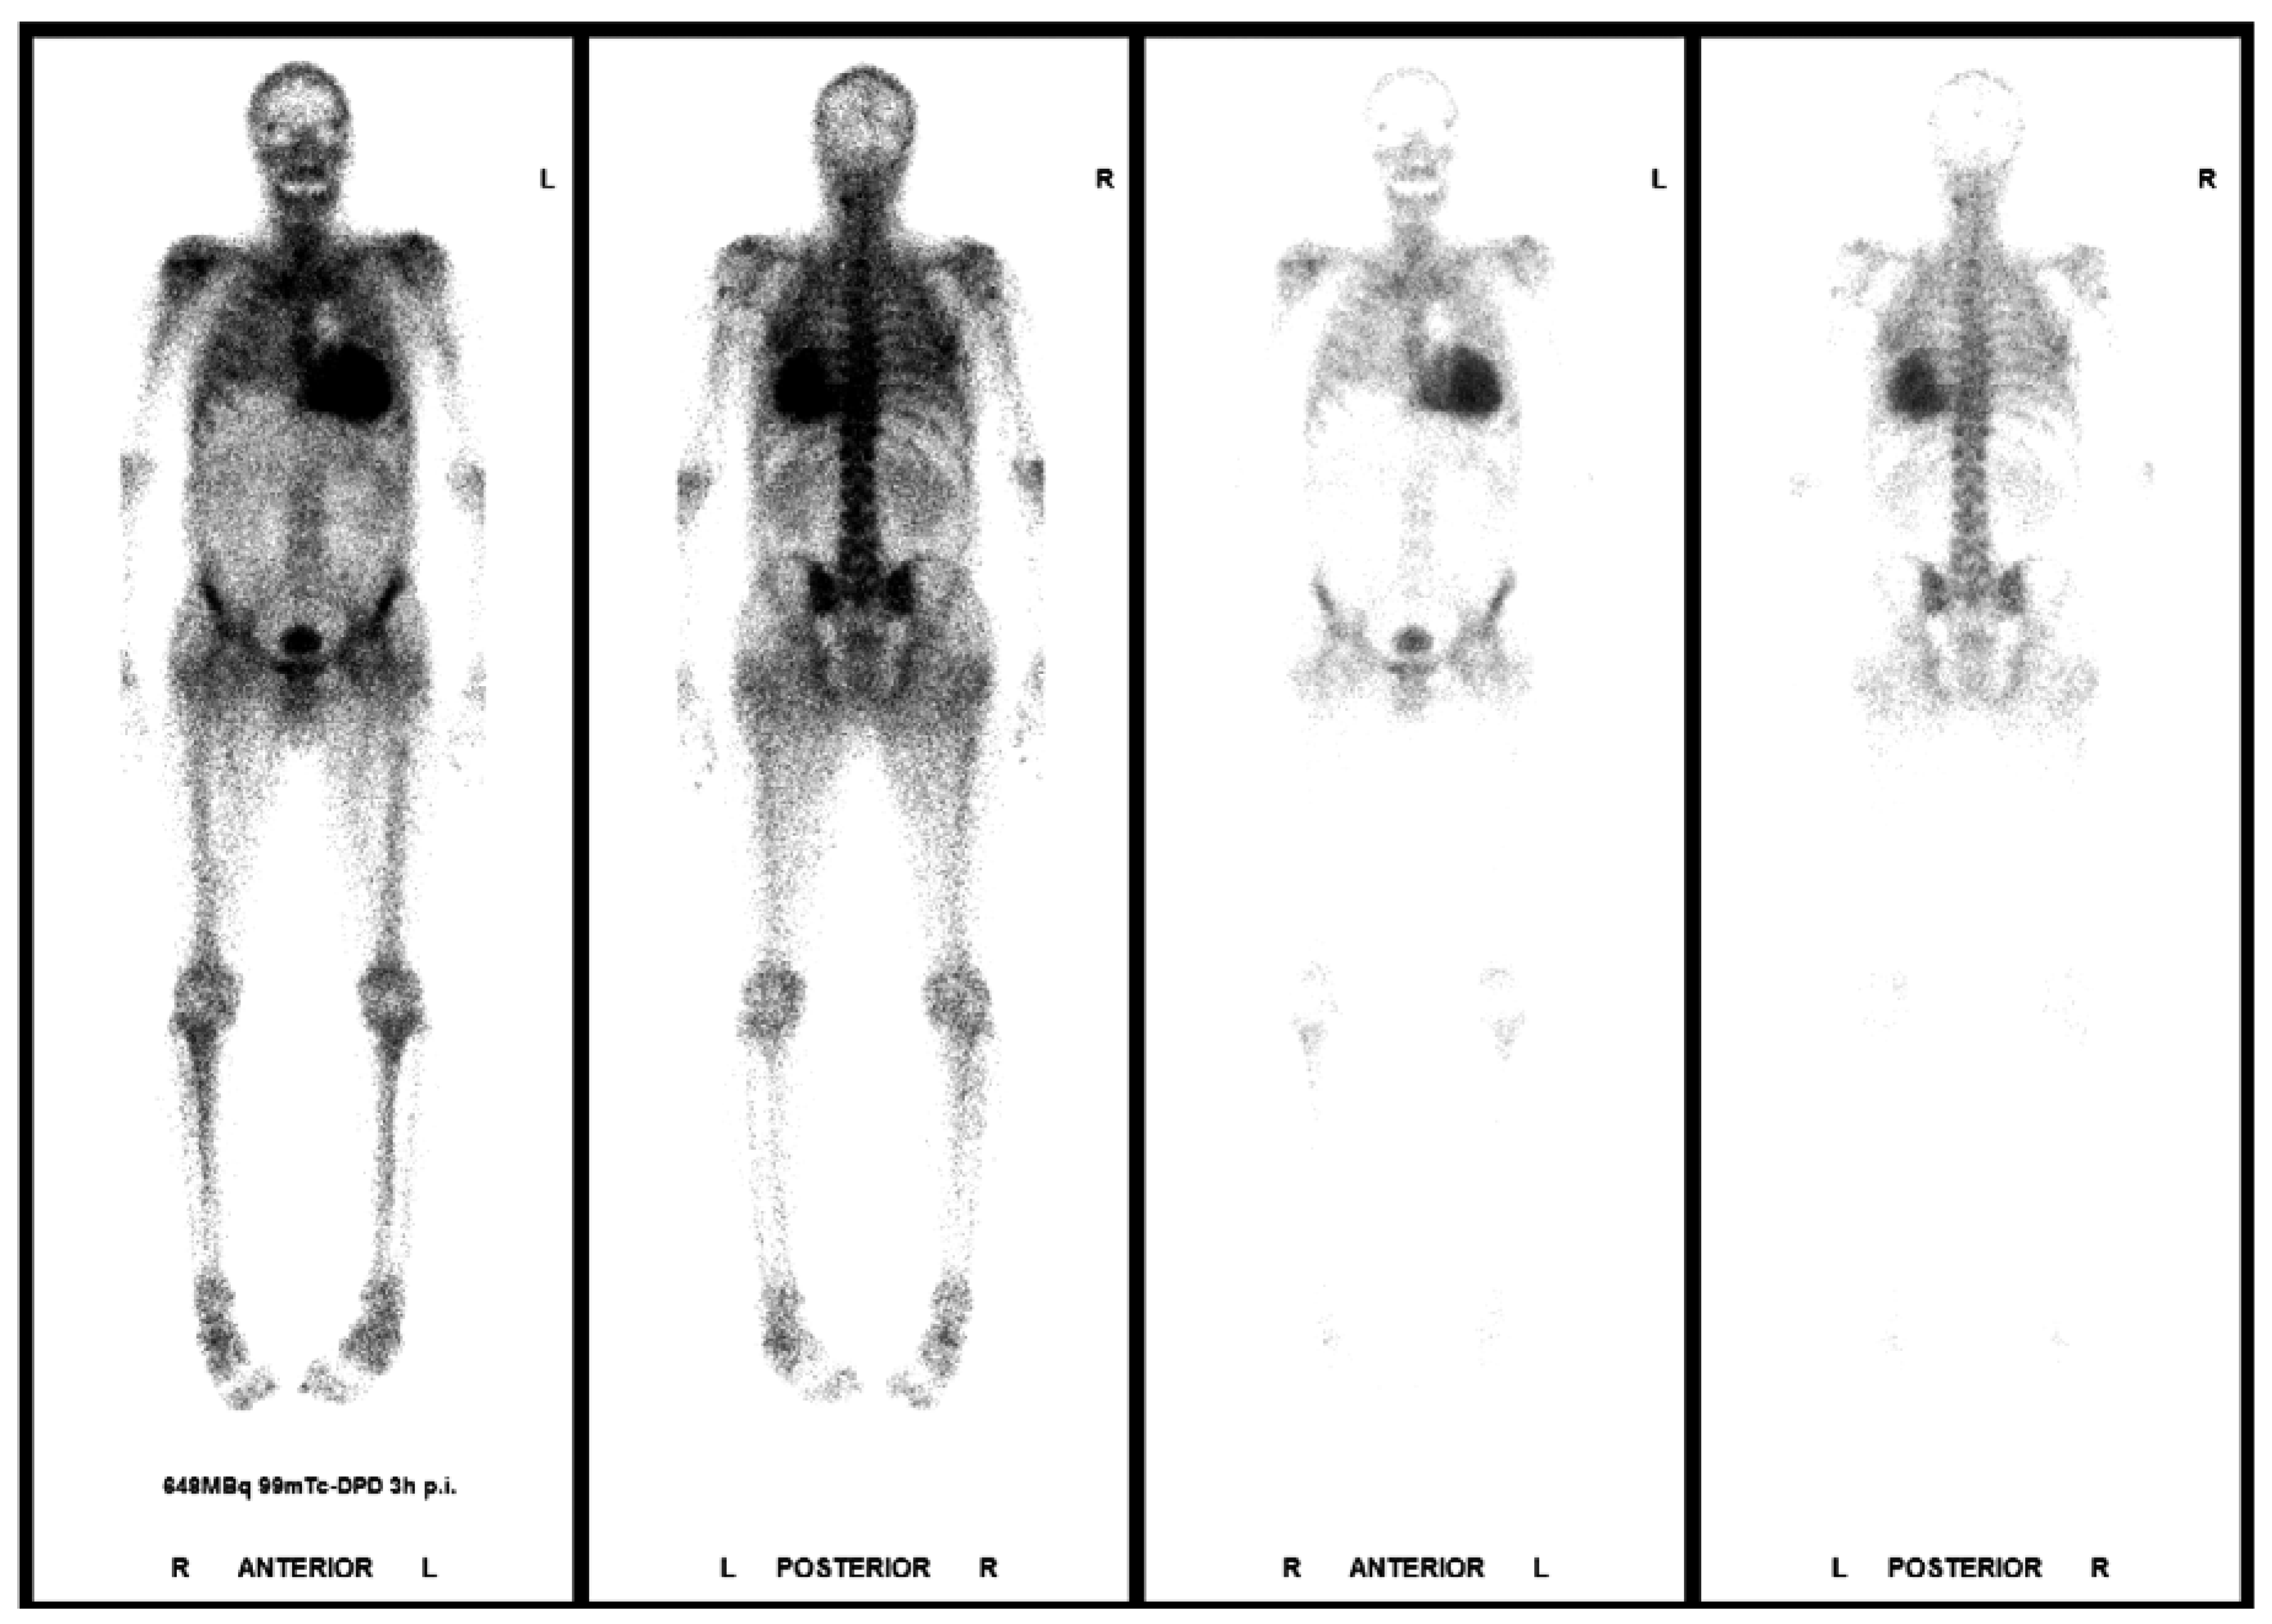

In the absence of plasma cell dyscrasia, bone scintigraphy with technetium-labelled bone-seeking radiopharmaceuticals is extremely useful in the diagnosis of ATTR amyloidosis, as the tracer strongly binds to amyloid composed of transthyretin, but much less to amyloid composed of immunoglobulin light chains [16,17]. In case of typical imaging (cardiac MRI or echocardiography), and strongly positive scintigraphy with no detectable monoclonal gammopathy, TTR amyloidosis can be diagnosed without performing a biopsy (Figure 7). Genetic testing will distinguish between the wild-type and mutant form of TTR amyloidosis. However, in the case of a negative scintigraphy and a persistent high suspicion of amyloidosis, again, endomyocardial biopsy should be performed. Although diagnosing amyloidosis in theory is straightforward, it is still a challenging diagnosis [18].

Figure 7. Technetium 99m-phosphate-scintigraphy showing a strong myocardial tracer uptake and thereby confirming the diagnosis of ATTR amyloidosis.